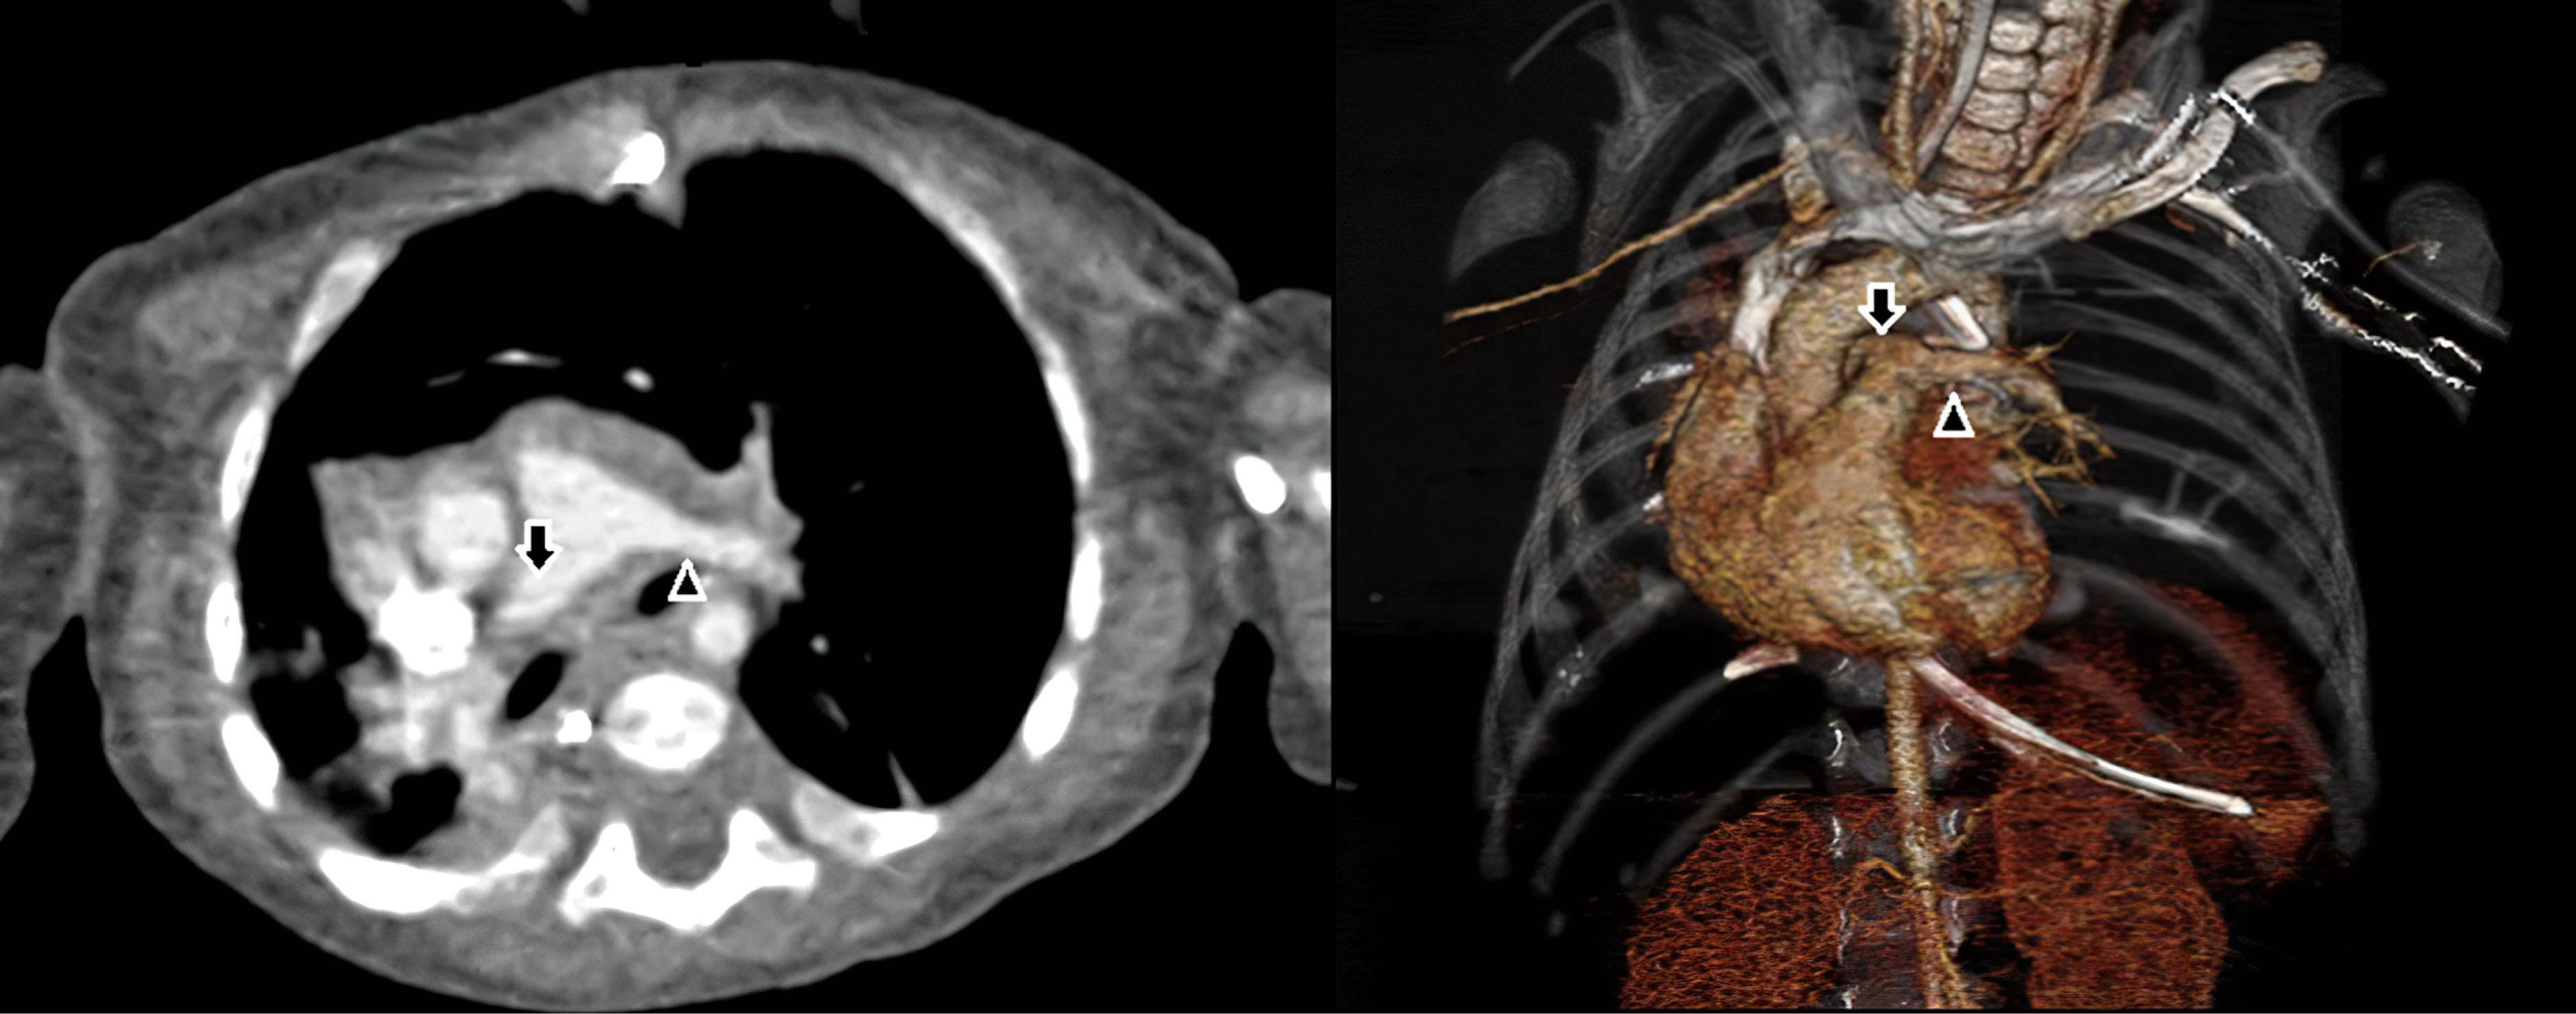

Figure 2.

Intraoperative view of branching of the left PA(black arrow) from right PA (arrowhead). B. Intraoperative view of branching of the left PA from the pulmonary trunk after anastomosis (white arrow), Left PA stump zone (black arrow)